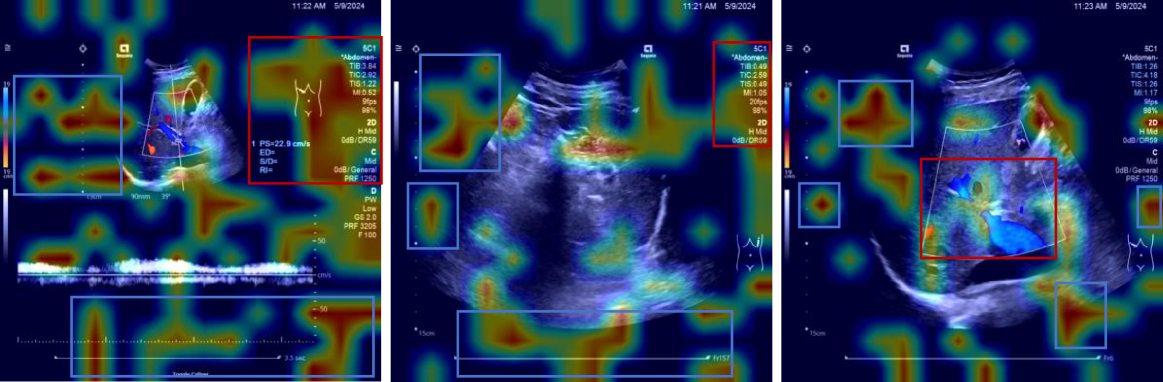

Visualization

To elucidate the internal decision-making process of VLMs, we employed the Grad-CAM heatmap visualization technique proposed by Zhang et al. (cam), where warmer regions (depicted in red) in Figure 6 indicate pixels exhibiting the strongest gradient flow towards the predicted token logit, signifying that the model primarily attends to these semantically significant regions during textual output generation, whereas cooler regions (in blue) receive negligible weight allocation, implying minimal contribution to the prediction; the visualized attention patterns confirm that the VLM’s language reasoning is grounded in semantically relevant visual features such as anatomical landmarks, quantitative measurements, and hemodynamic bar charts—highlighted within red bounding boxes—rather than spurious correlations, yet the model also exhibits attention to non-informative regions including image edges and black areas—highlighted within blue bounding boxes—which lack semantic utility, thereby highlighting a persistent challenge in VLMs: the coexistence of semantic consistency (focusing on task-critical visual elements) and spurious associations (distracting attention to noise or irrelevant artifacts); future work should enhance model robustness and interpretability through strategies such as attention regularization, constrained attention routing, and explicit mitigation of spurious associations.

Refer to caption

(a)

(b)

(c)

(d)

(e)

(f)

(g)

Figure 6: Visualization results. Red boxes highlight meaningful regions, while blue boxes indicate irrelevant or meaningless areas.